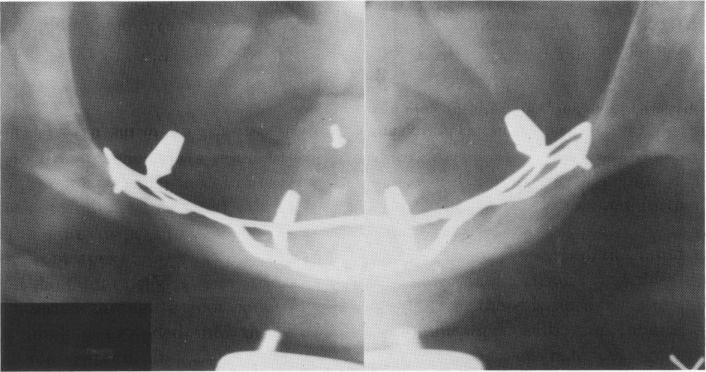

Fig. 12-110. A subperiosteal implant was fabricated for the mandible. Note the absence of bone below the sinus in the maxilla.

2 Subperiosteal implant fabricated for mandible & no bone below sinus